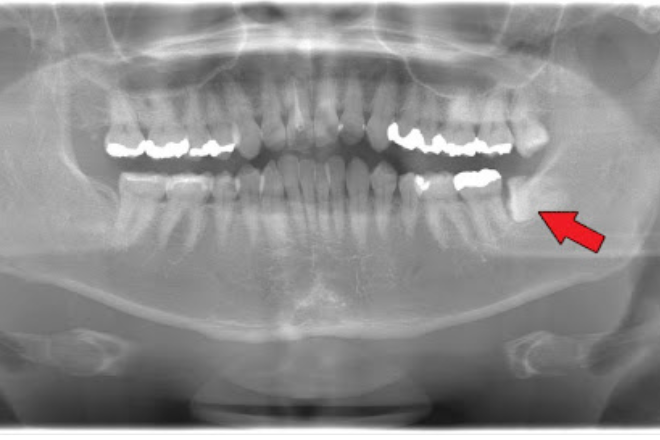

1.横向き・斜めに生えている場合

親知らずが横向きや斜めに生えていると、抜歯を提案されることが多くなります。

親知らずは口の一番奥に位置するため、まっすぐ生えていても歯ブラシが届きにくい場所です。

横向き・斜めの状態だとさらに清掃が困難になり、汚れが溜まりやすいです。

その結果、虫歯や歯周病を発症するリスクが上がってしまいます。

また横向きに生えた親知らずが手前の歯を圧迫し、歯の根を溶かしてしまうケースもあります。

周りの歯の健康を守るためにも、早めの抜歯が望ましいでしょう。

3.隣の歯に悪影響を与えている

親知らずが水平方向に生えてくることがあります。

この場合、親知らずが隣の歯を押してしまい、痛みが生じる可能性があります。

押された歯は徐々にダメージを受け、将来的に歯並びの乱れや歯の寿命を縮める原因にもなりかねません。